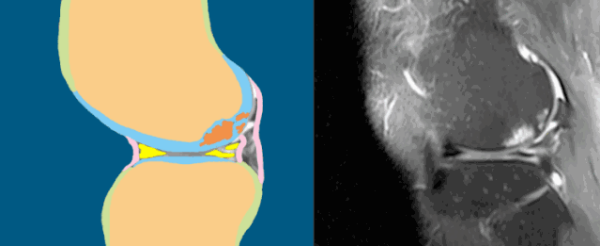

膝关节半月板损伤导致关节软骨磨损

关节软骨损伤